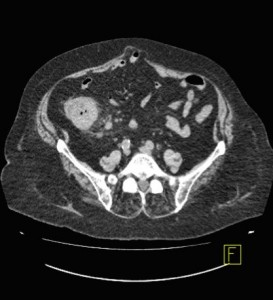

El estudio complementario que pediríamos sería un TAC abdominal simple, ya que nos proporciona una gran cantidad de información, es sencillo y rápido de realizar a la paciente, y como no sabemos con exactitud lo que le ocurre es lo más apropiado para obtener más información y averiguar lo que le sucede a la paciente. El estudio de tránsito no estaría indicado porque no presenta signos de alteración de la motilidad o tránsito.